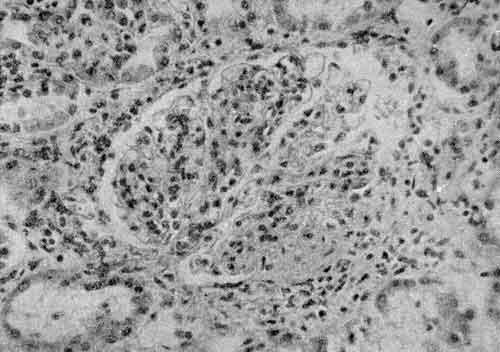

Информация о диссеминированном рассеянном энцефаломиелите